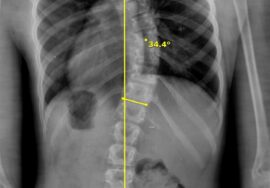

الجنف (Scoliosis)

انحناء جانبي غير طبيعي للعمود الفقري، قد يظهر عند الأطفال أو المراهقين، وأحيانًا عند البالغين نتيجة عوامل تنكسية.

الأشعة السينية (X-ray): لتحديد درجة الانحناء أو التشوه.